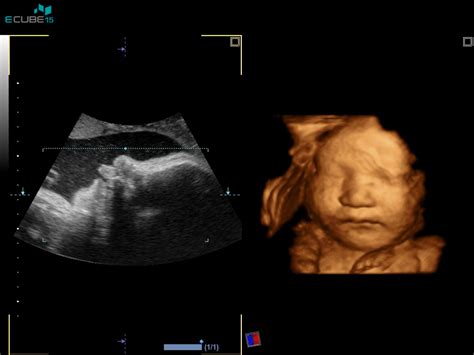

- 12. teden nosečnosti: Plod meri 5,4 cm (kot sliva) in tehta 14 g. Srce deluje kot pri odraslem, centralno živčevje pa se razvija. Maternica je velikosti grenivke. Imuniteta nosečnice se naravno zmanjša, kar koristi rastočemu plodu.

- 13. teden nosečnosti: Plod meri 7,4 cm (kot breskev) in tehta do 23 g. Glavica še vedno predstavlja polovico dolžine ploda, a okončine hitro rastejo. Jutranje slabosti se pogosto umirjajo, lahko pa se pojavi zgaga.